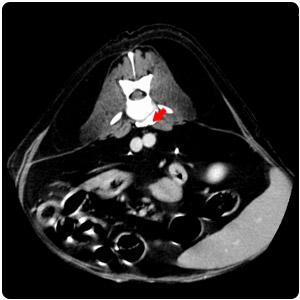

| Hernia |

脊椎旁腫塊(黃)、脾腫塊(紅) |